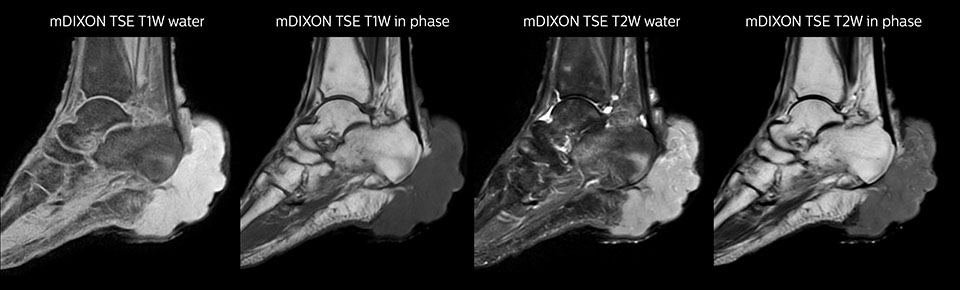

MR-Untersuchung mit Prodiva 1.5T, 72-jährige Patientin mit malignem Melanom am Knöchel. mDIXON TSE bietet eine hervorragende Fettsuppression ohne Verzerrung, wie sie ansonsten bei diesen Extremitäten häufig auftritt.

Auch im Allgemeinkrankenhaus Seirei Mikatahara in der Präfektur Shizuoka in Japan zeigt Prodiva 1.5T Wirkung. Der Radiologe Dr. Takahashi und seine Kollegen in der grossen Radiologieabteilung arbeiten mit drei MR-Scannern, u.a. einem Ingenia 3.0T, für Untersuchungen einer Population mit vielen älteren Patienten. Als Ersatz für ein älteres MR-System entschied man sich für Prodiva 1.5T – und die klinischen Funktionen und Vorteile im Arbeitsablauf des neuesten Scanners haben grosse Wirkung gezeigt. Dr. Takahashi sagt: „Für ein 1.5T-System liefert Prodiva ausgezeichnete Qualität, die meine Erwartungen noch übertroffen hat. Inzwischen machen wir einige Untersuchungen, die wir vorher nur auf einem 3T-System ausgeführt hätten, mit Prodiva.“ Ein hohes Signal-Rausch-Verhältnis, Bewegungsunterdrückung und eine hervorragende Homogenität des Magnetfelds unterstützen ausgezeichnete Ergebnisse für das Team. „Ich bin besonders beeindruckt von der Qualität der Fettsuppression mit mDIXON XD, vor allem im Halsbereich und bei Gelenken der Extremitäten, die für uns häufig problematisch waren“, erläutert Dr. Takahashi. „Seit wir Prodiva haben, mussten wir aufgrund des hohen SNR, der Bewegungsunterdrückung und der hervorragenden Homogenität des Magnetfelds weniger Wiederholungsscans durchführen.“ Dr. Takahashi setzt Prodiva 1.5T für eine Vielzahl von Untersuchungen ein, u.a. Herz, Gefässe, Abdomen und muskuloskelettale Anwendungen. Darüber hinaus führt er auch Ganzkörperuntersuchungen mit T1, STIR, T2WI und Diffusionssequenzen auf dem Prodiva System durch. „Ich bin beeindruckt von der kurzen Vorbereitungszeit der Patienten und der schnellen Scandauer“, betont er. „Normalerweise ist die Diffusionsbildgebung des Körpers aufgrund von Verzerrungen sehr anspruchsvoll. Mit Prodiva erzielen wir hier sehr gute Ergebnisse.“